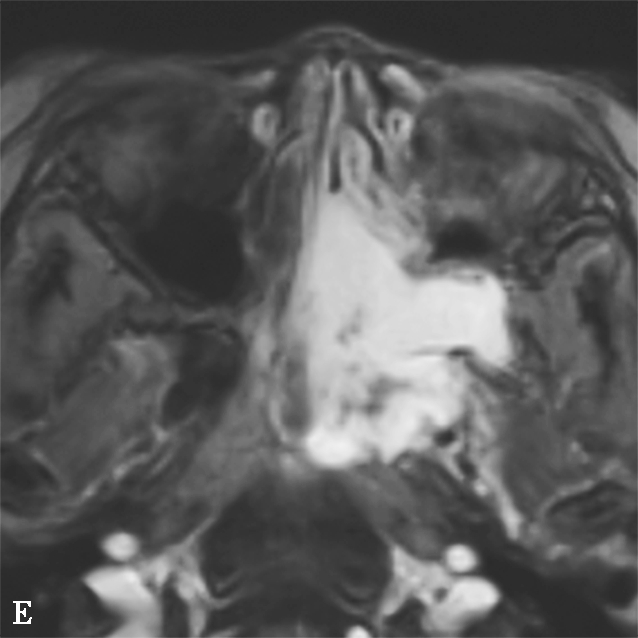

图1-2-6 左侧颈内动脉创伤后假性动脉瘤突入蝶窦

患者男,36岁,车祸伤后左侧额部硬膜外血肿清除并颅骨去骨瓣减压术后半年,间断大量鼻出血半个月就诊。A.颅脑CTA检查MPR横断面重组,可见蝶窦内软组织密度影,部分与颈内动脉同步均匀强化,并通过蝶窦骨质缺损与海绵窦游离段颈内动脉内侧壁相连,蝶窦内病变前缘部分未见强化;B.CPR(曲面重组)重建,示假性动脉瘤瘤体与邻近颈内动脉以宽基底相连,骨折断端与颈内动脉壁关系密切;C.CTA VR重建,示瘤体与左侧颈内动脉海绵窦段相连;D.左侧颈内动脉DSA检查可见海绵窦段假性动脉瘤显影,因瘤体盗血致其远端分支显影不满意